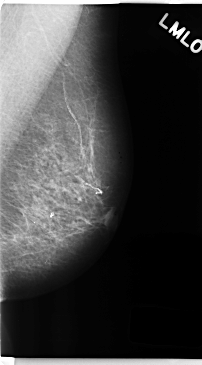

C_0195_1.LEFT_MLO

LEFT_MLO LINES 4736 PIXELS_PER_LINE 2616 BITS_PER_PIXEL 12 RESOLUTION 50 NON_OVERLAY